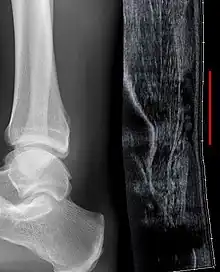

Although a tear may be diagnosed by history and physical exam alone, an ultrasound scan is sometimes required to clarify or confirm the diagnosis. Once diagnosis is made, ultrasound imaging is an effective way to monitor the healing progress of the tendon over time. An ultrasound is recommended over MRI and MRI is generally not needed.[13][16] Both MRI and ultrasound are effective tools and have their strengths and limitations. However, when it comes to an Achilles tendon tear, an ultrasound is usually recommended first because of convenience, quick availability, and cost.[17]

Imaging

Ultrasonography can be used to determine the tendon thickness, character, and presence of a tear. It works by sending harmless high frequencies of sound waves through the body. Some of these sound waves reflect back off the spaces between fluid and soft tissue or bone. These reflected images are analyzed and created into an image. These images capture in real time and are helpful in detecting movement of the tendon and visualizing injuries or tears. This device makes it possible to identify injuries and observe healing over time. Ultrasound is inexpensive and involves no harmful radiation. It is operator-dependent and so requires a level of skill and practice for it to be used effectively.[17]

MRI can be used to distinguish incomplete ruptures from degeneration of the Achilles tendon. MRI can also distinguish between paratenonitis, tendinosis, and bursitis. This technique uses a strong uniform magnetic field to align millions of protons running through the body. These protons are then bombarded with radio waves that knock some of them out of alignment. When these protons return they emit their own unique radio waves that is analyzed by a computer in 3D to create a sharp cross sectional image of the area. MRI provides excellent soft tissue imaging making it easier for technicians to spot tears or other injuries.[18]

Radiography can also be used to indirectly identify Achilles tendon tears. Radiography uses X-rays to analyze the point of injury. This is not very effective at identifying soft tissue injuries. X-rays are created when high energy electrons hit a metal source. X-ray images are acquired by utilizing the different densities of the bone or tissue. When these rays pass through tissue they are captured on film. X-rays are generally best for dense objects such as bone while soft tissue is shown poorly. Radiography is not the best for assessing an Achilles tendon injury. It is more useful for ruling out other injuries such as heal bone fractures.[16]